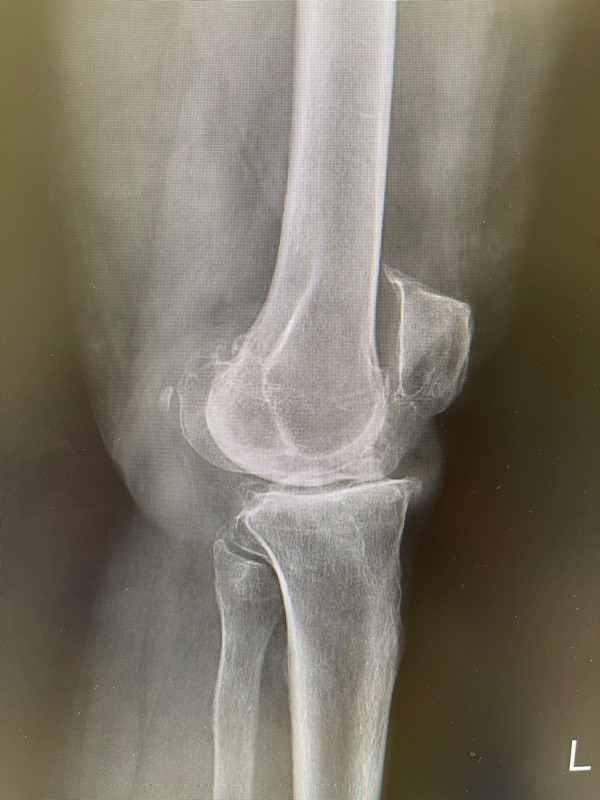

✔ เอกซเรย์

ดูว่ามีข้อเสื่อมหรือกระดูกงอกหรือไม่